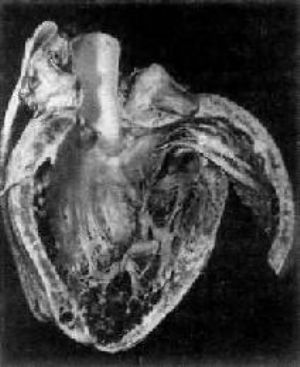

病理学/克山病

图7-30 克山病左心室明显扩张,室壁变薄